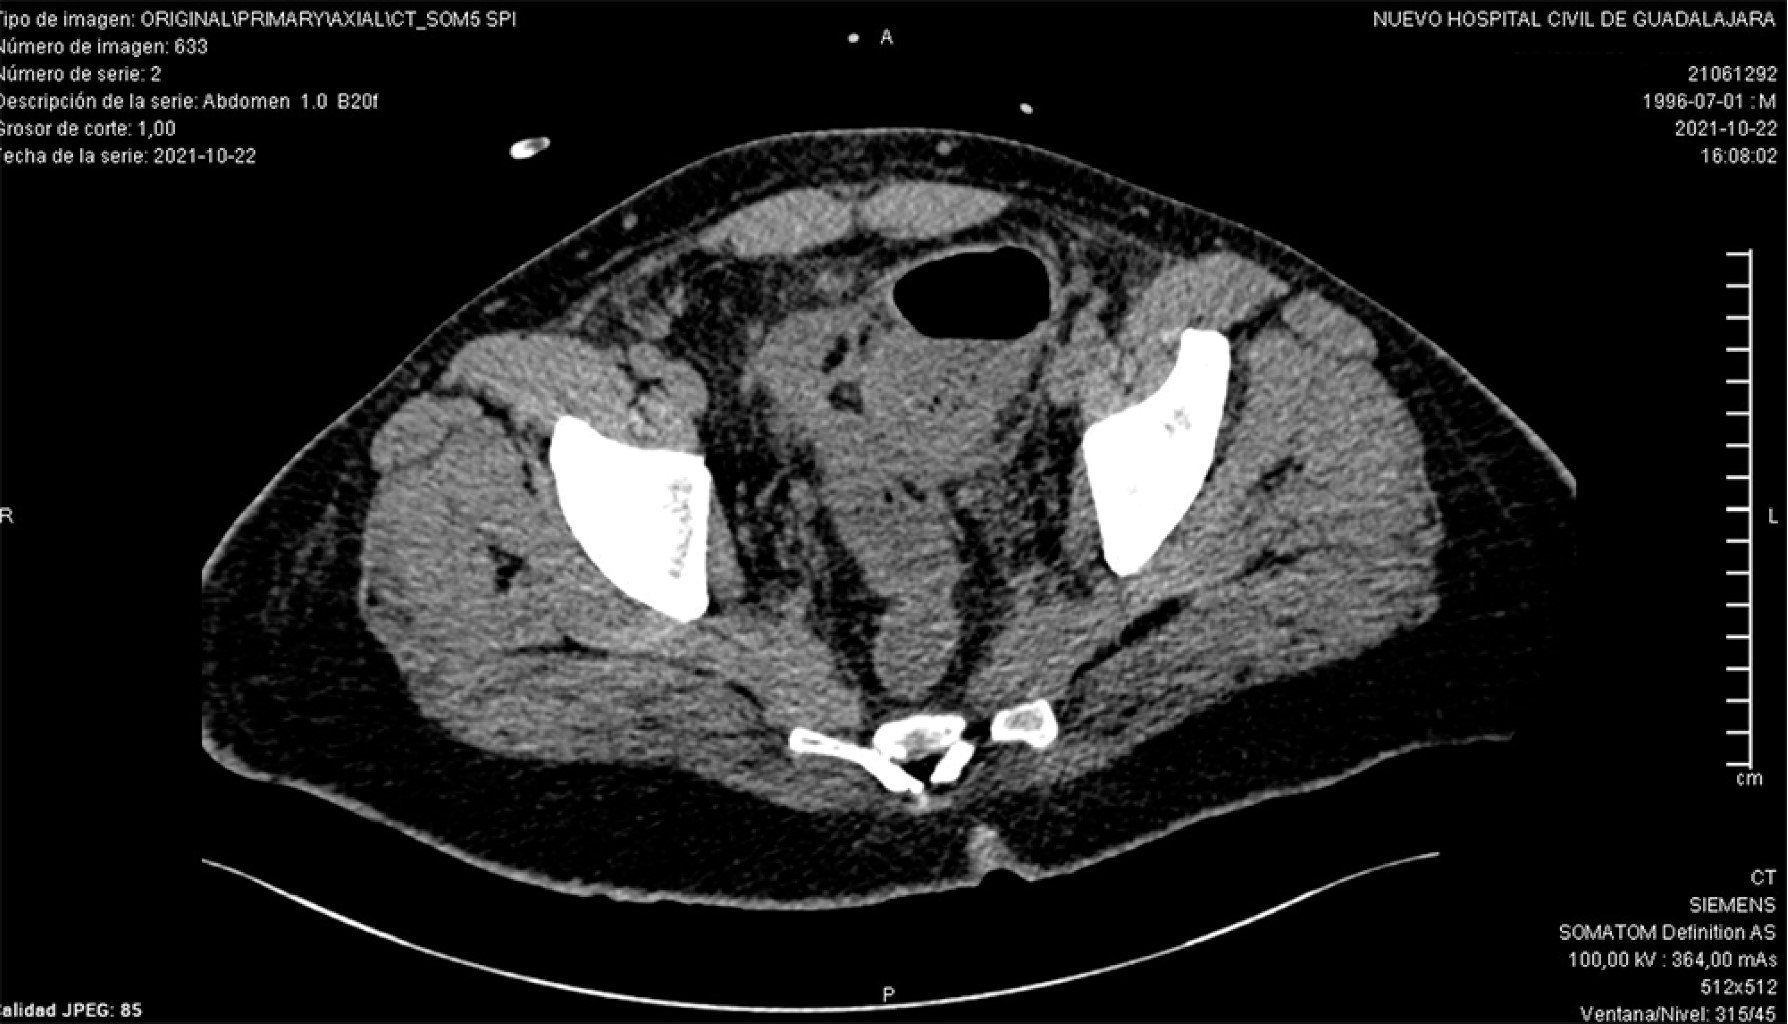

Introduction: rectal cancer can occur in young patients with no family history, so it is important to assess screening studies in the young population. Clinical case: 25-year-old male with no family history, goes to the emergency department due to a distal bowel obstruction with a history of 30 kg weight loss and diarrhea of six months' duration, imaging studies with an upper rectal lesion and secondary liver nodules. Discussion: results from studies worldwide support the benefits of changing the age of screening for colorectal cancer for patients of any age. The implementation of screening is intended to reduce mortality, but not incidence rates. Conclusions: it is necessary to take into account and assess the signs and symptoms of young patients who come to the consult with symptoms suggestive of a tumor and not wait for them to arrive at an emergency department with data of distal large intestine occlusion and think that cancer can be present also in young patients.

Figure 5